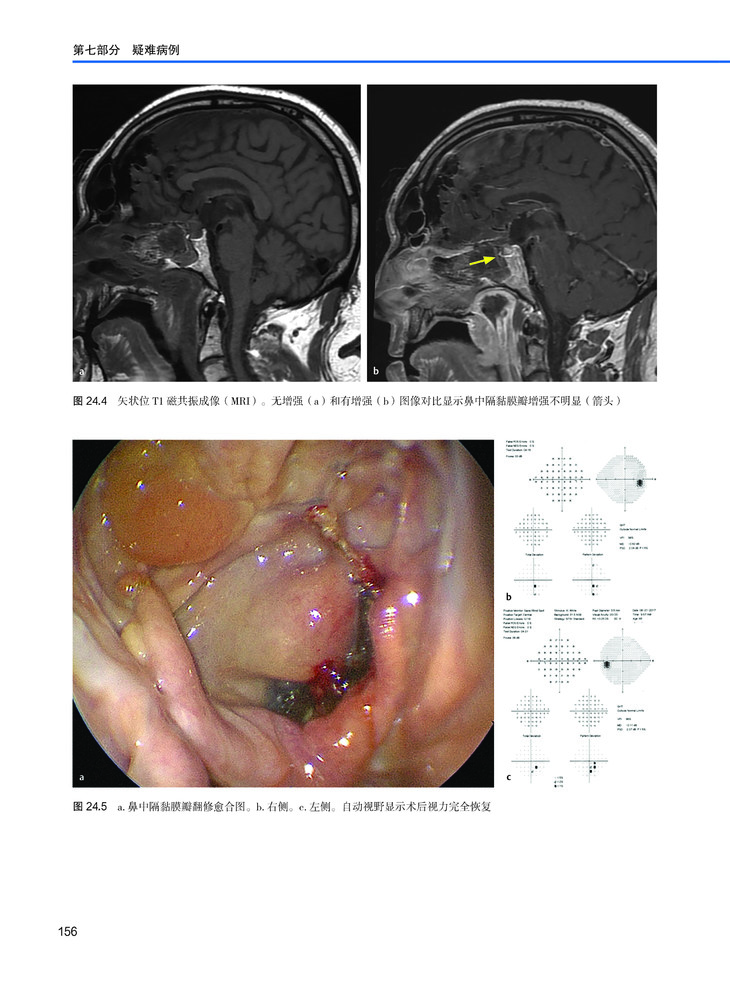

本书原著由梅奥医学中心的Carlos D. Pinheiro-Neto 和 Maria Peris-Celda 教授主编,系统性总结了内镜下颅底重建方法并展示了大量经典病例,编者涉及神经外科、耳鼻喉科以及头颈外科等专科的专家。本书虽篇幅不长,却能够将颅底重建这一临床常见且棘手的问题进行系统性总结,并且书中图文并茂,理论联系实践,非常值得神经外科、耳鼻喉科从事颅底外科手术的临床一线工作的医生借鉴学习。

本书可作为多学科专家的内镜颅底重建经典指南。由于耳鼻喉科医生和神经外科医生之间的密切合作,内镜鼻腔神经外科手术已成为成功治疗各种颅底病变的外科设备的一部分。今天,它被认为是许多类型颅底肿瘤的金标准外科技术。耳鼻喉科先驱Carlos D.Pinheiro-Neto和神经外科医生Maria Peris Celda共同编撰了本书,书中涵盖了过去20年中最重要的内镜颅底重建技术。